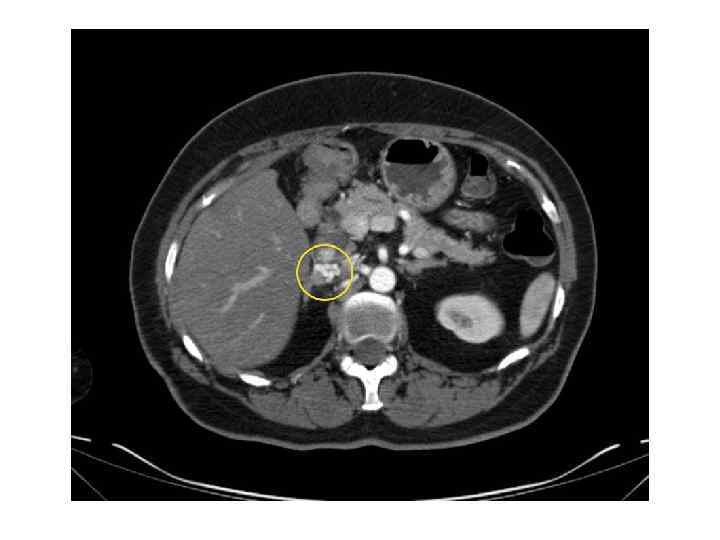

Диагностика • Методы визуализации надпочечников: 1) КТ 2) МРТ 3) ПЭТ 4) Ультразвуковое исследование • Клиническая картина • Гормональное обследование • Пункционная биопсия

КТ и МРТ признаки ДОНП АКР Метастаз Размер < 3 см > 4 см < 3 см (обычно) Форма Округлая, четкий контур Неправильная, нечеткий контур Овальная; нечет- кий, прерывистый контур Сторона выявления Одиночная или двусторонняя Чаще двусторонний Рост < 1 см в год > 2 см в год Различный Структура Гомогенная Гетерогенная, с участками различной плотности Гетерогенная с участками различной плотности

КТ и МРТ признаки (2) ДОНП АКР Метастаз < 10 HU >10 -25 HU Васкуляризация в контрастную фазу + + Изменение плотности через 10 минут выведения контраста >50% <50% Некрозы, кальцинаты, кровоизлияния Редко Часто Не всегда Неконтрастная плотность «Инциденталома надпочечника. Методические рекомендации для врачей первичного звена» под редакцией Дедова И. И. , Мельниченко Г. А.